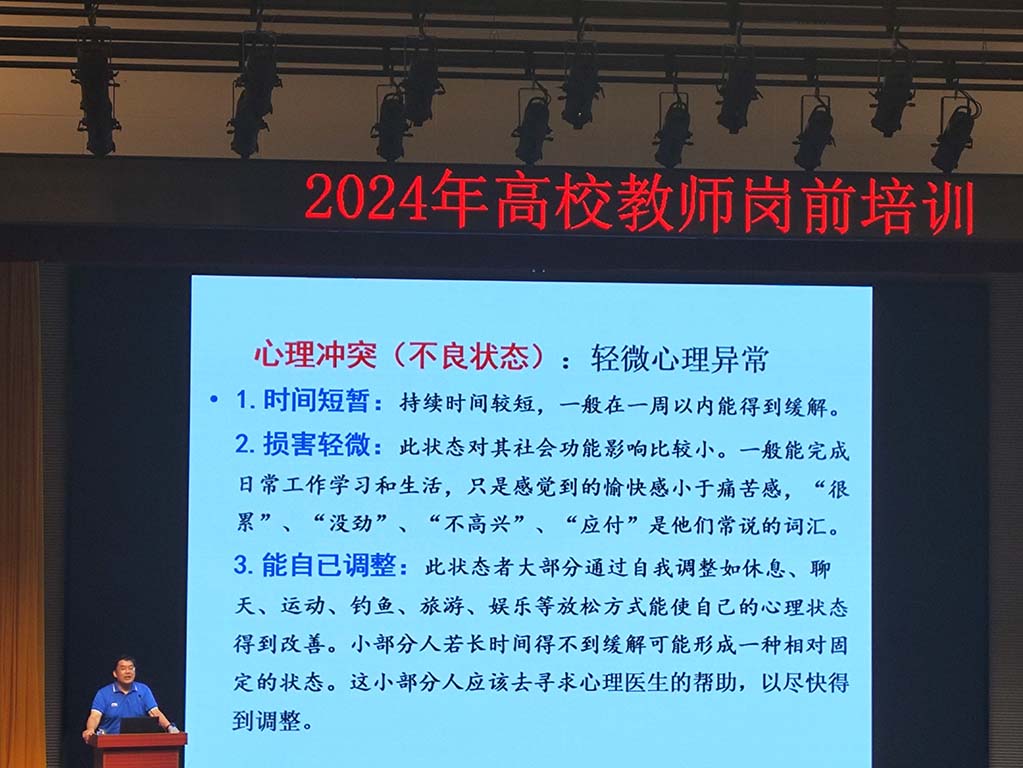

1、运动、说话、良好睡眠、避免不良人际冲突

三分钟呼吸空间

1、放松状态,找一个自己正式的状态,感受你周围

2、深呼吸,注意力在你的呼吸鼻尖

3、感受所有的存在

整个过程不评判,让它在那里。

改善睡眠,减轻疼痛,焦虑

睿星疗法小程序